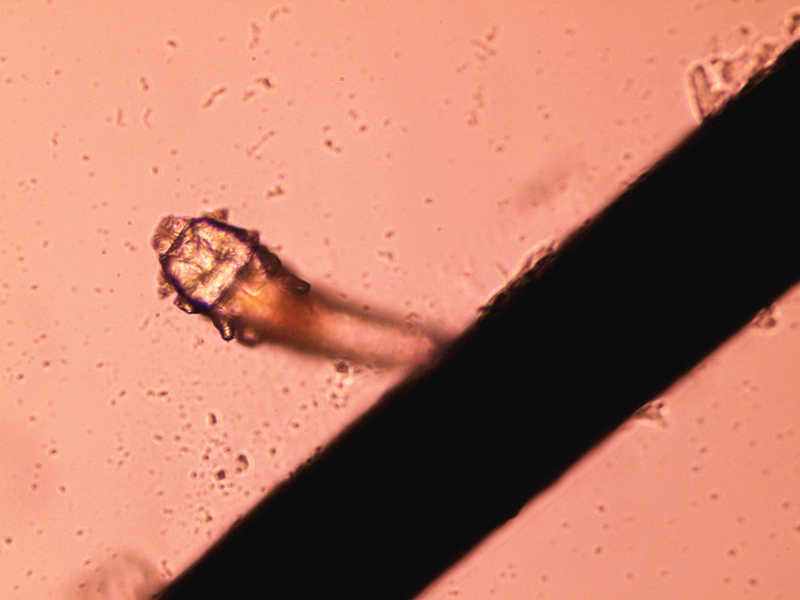

“你的眼瞼上有寄生蟲!”被別人這樣說你一定會受到很大的沖擊吧。不過,這可不是危言聳聽,據資料統計,我國人體蠕形螨的感染率較高,據報道最高達到98%以上。因為人體對螨蟲的感染無免疫性,不同年齡,不同民族,不同性別均可感染。蠕形螨廣泛存在于自然界,迄今只有兩個種類發現寄居于人體體表,即毛囊蠕形螨和皮脂蠕形螨。而寄居在人類眼瞼上的睫毛蠕形螨以食睫毛毛囊上皮細胞和代謝產物為生,其代謝廢物和死亡軀體常導致睫毛根部圓柱狀或袖套樣鱗屑,導致瞼緣炎。

蠕形螨寄居眼部臨床表現輕重不一,從無任何不適到瞼緣充血,癢,刺痛感,異物感等瞼緣炎典型體征,蠕形螨導致的瞼緣炎常反復發作,難徹底治愈,在瞼緣常發現鱗屑存在。因此,當你發現頑固不愈,反復發作的鱗屑性瞼緣炎,必需警惕蠕形螨感染的可能。